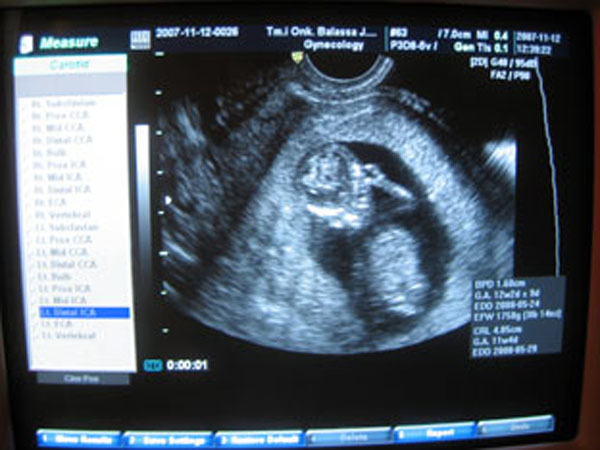

Christell, Bruncvikdokiról nyilatkozzanka a többiek. Örülök az adataidnak! Legközelebb már biztos látják a nemét is a babádnak! Mikor mész újra dokihoz?